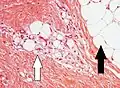

Lipoblasts (white arrow) and lipocytes (black arrow), in a case of lipoblastoma

Lipoblasts are seen in liposarcoma[7] and characteristically have abundant multivacuolated clear cytoplasm and a dark staining (hyperchromatic), indented nucleus.

Lipid-laden histiocytes may mimic lipoblasts, but have lightly eosinophilic cytoplasm and a small normochromatic nuclei which are not hollowed out from the lipid vacuoles.[6]